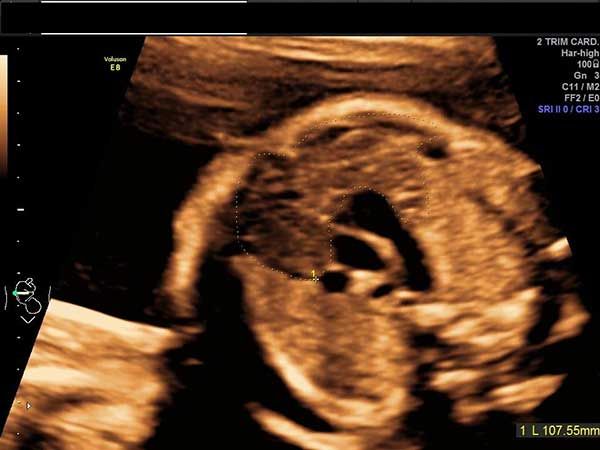

A routine ultrasound exam reveals unexpected findings in the lungs of a 29-week fetus. What’s your diagnosis?

Challenge your diagnostic skills: Can you identify this structure in the fetal thorax?